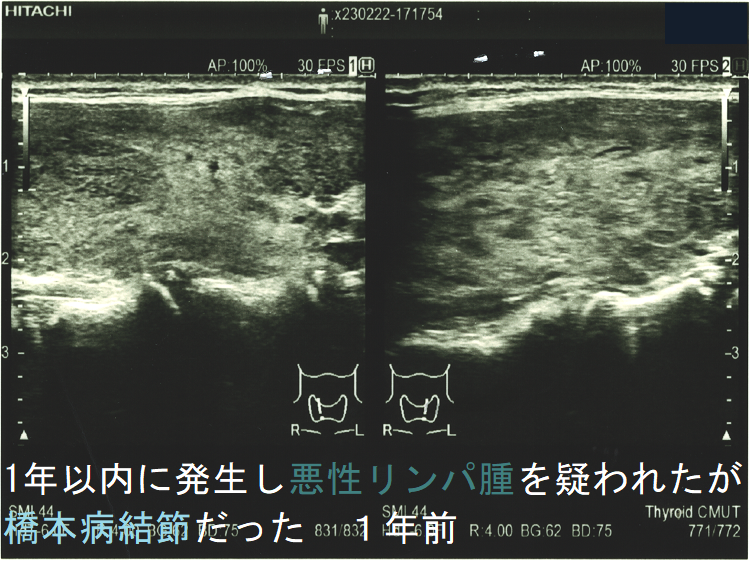

![1年以内に現れ悪性リンパ腫が疑われたが橋本病結節だった 1年前 (水平断)[拡大] 1年以内に現れ悪性リンパ腫が疑われたが橋本病結節だった 1年前 (水平断)[拡大]](../images/special/thyroid2/images20251130213537.png)